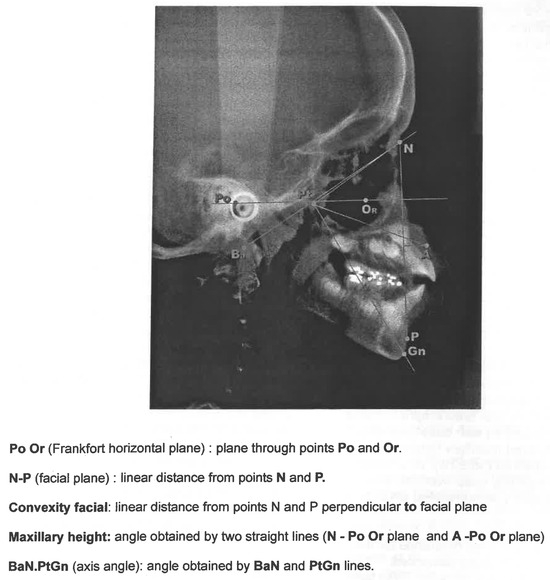

The tongue trust and anterior projection through the dental arcades during swallowing is known as Adapted Swallowing (AS) and is a common finding during mixed dentition. The authors studied the morphologic dentofacial characteristics through cephalom...